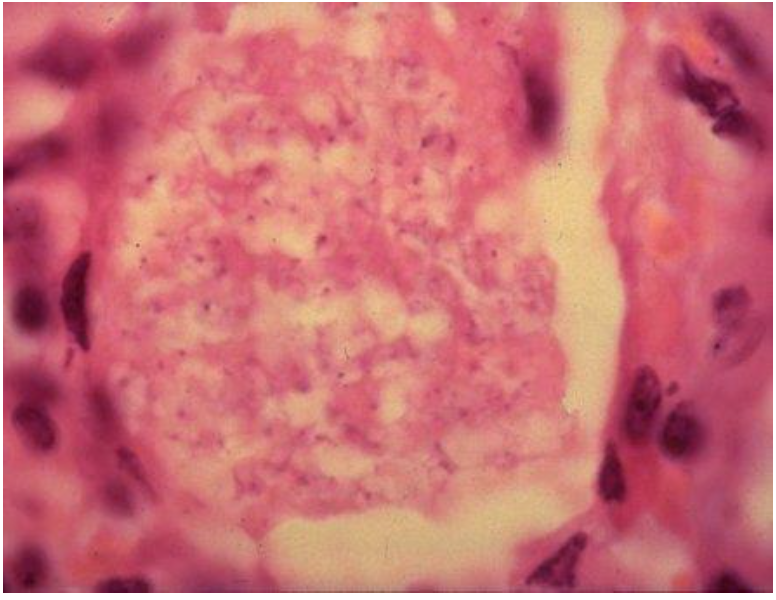

what is this?

acanthamoeba cyst in GAE brain tissue. (note mostly diagnosed at post mortem)